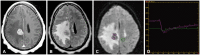

The imaging and clinical management of patients with brain tumor continue to evolve over time and now heavily rely on physiologic imaging in addition to high-resolution structural imaging. Imaging remains a powerful noninvasive tool to positively impact the management of patients with brain tumor. This article provides an overview of the current state-of-the art clinical brain tumor imaging. In this review, we discuss general magnetic resonance (MR) imaging methods and their application to the diagnosis of, treatment planning and navigation, and disease monitoring in patients with brain tumor. We review the strengths, limitations, and pitfalls of structural imaging, diffusion-weighted imaging techniques, MR spectroscopy, perfusion imaging, positron emission tomography/MR, and functional imaging. Overall this review provides a basis for understudying the role of modern imaging in the care of brain tumor patients.